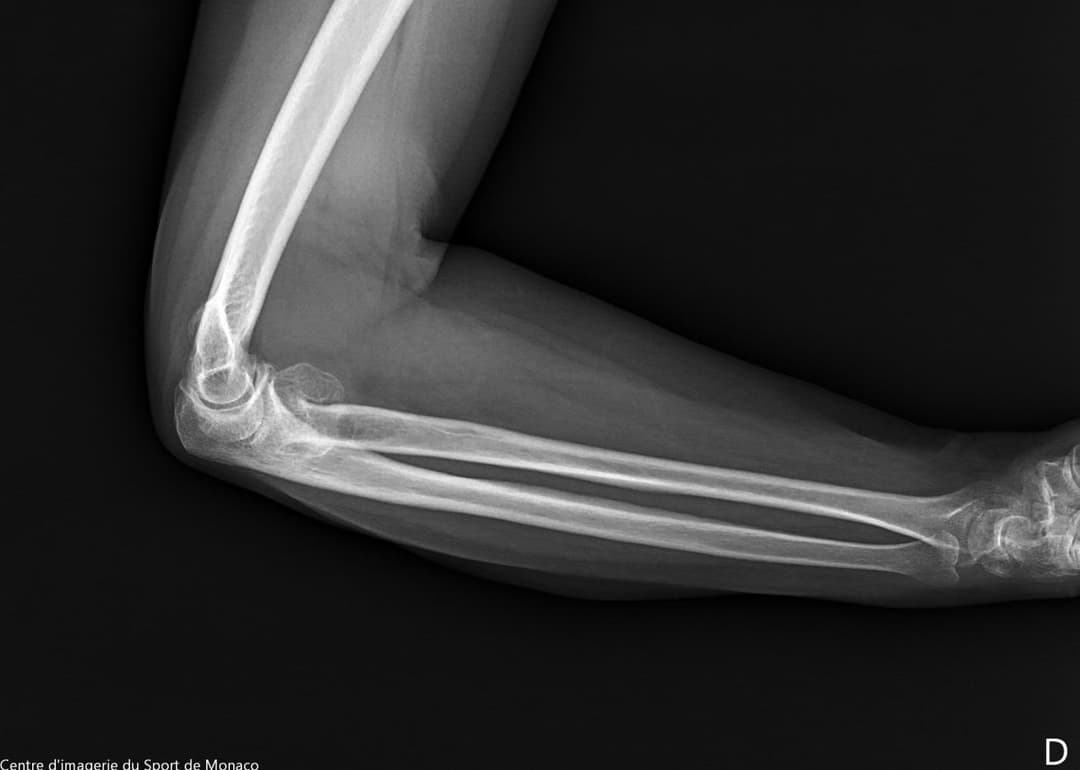

Radiographie

Excroissance osseuse au niveau métaphysoépiphysaire de la tête radiale qui évoque un ostéochondrome à large base d’implantation

Aspect post chirurgical de résection de la tête radiale.